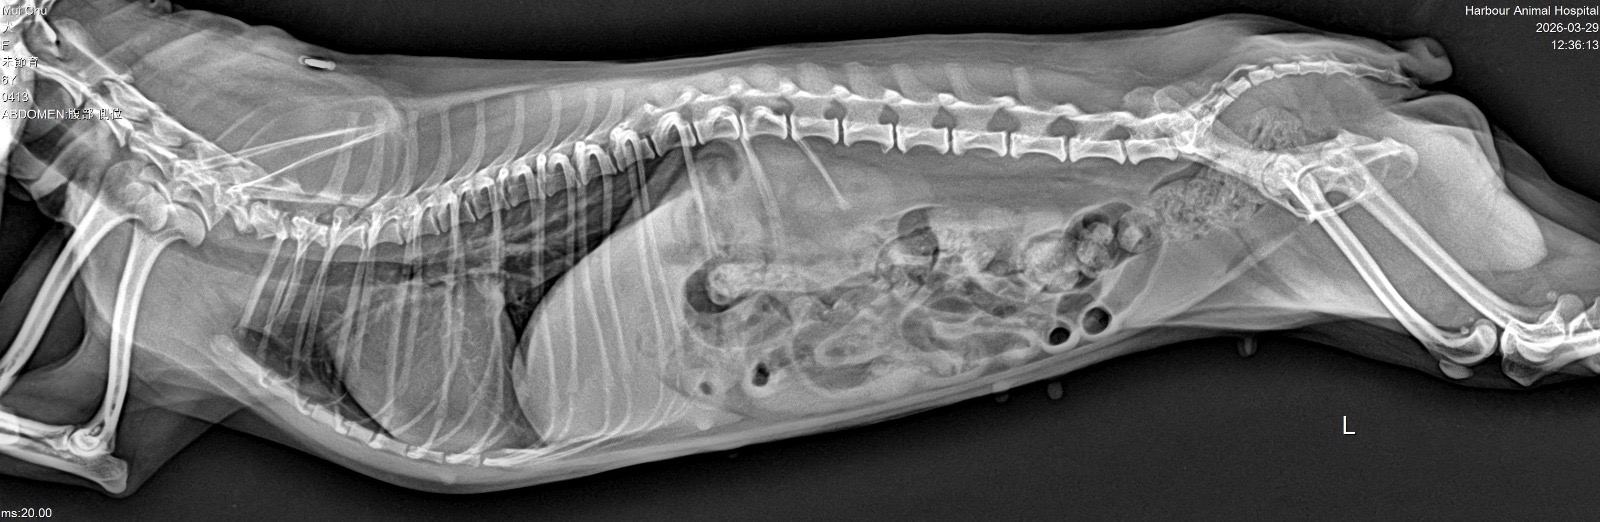

妹豬睇醫生 Get link Facebook X Pinterest Email Other Apps March 29, 2026 由於妹豬忍尿問題已有一段時日,星期六帶妹豬的尿去驗,夜間獲通知有晶石,所以星期日需帶妹豬去檢查!蔽日帶妹豬去診所照X光,萬幸無結石,只需食藥,但將來要留意骨刺的問題 Get link Facebook X Pinterest Email Other Apps Comments